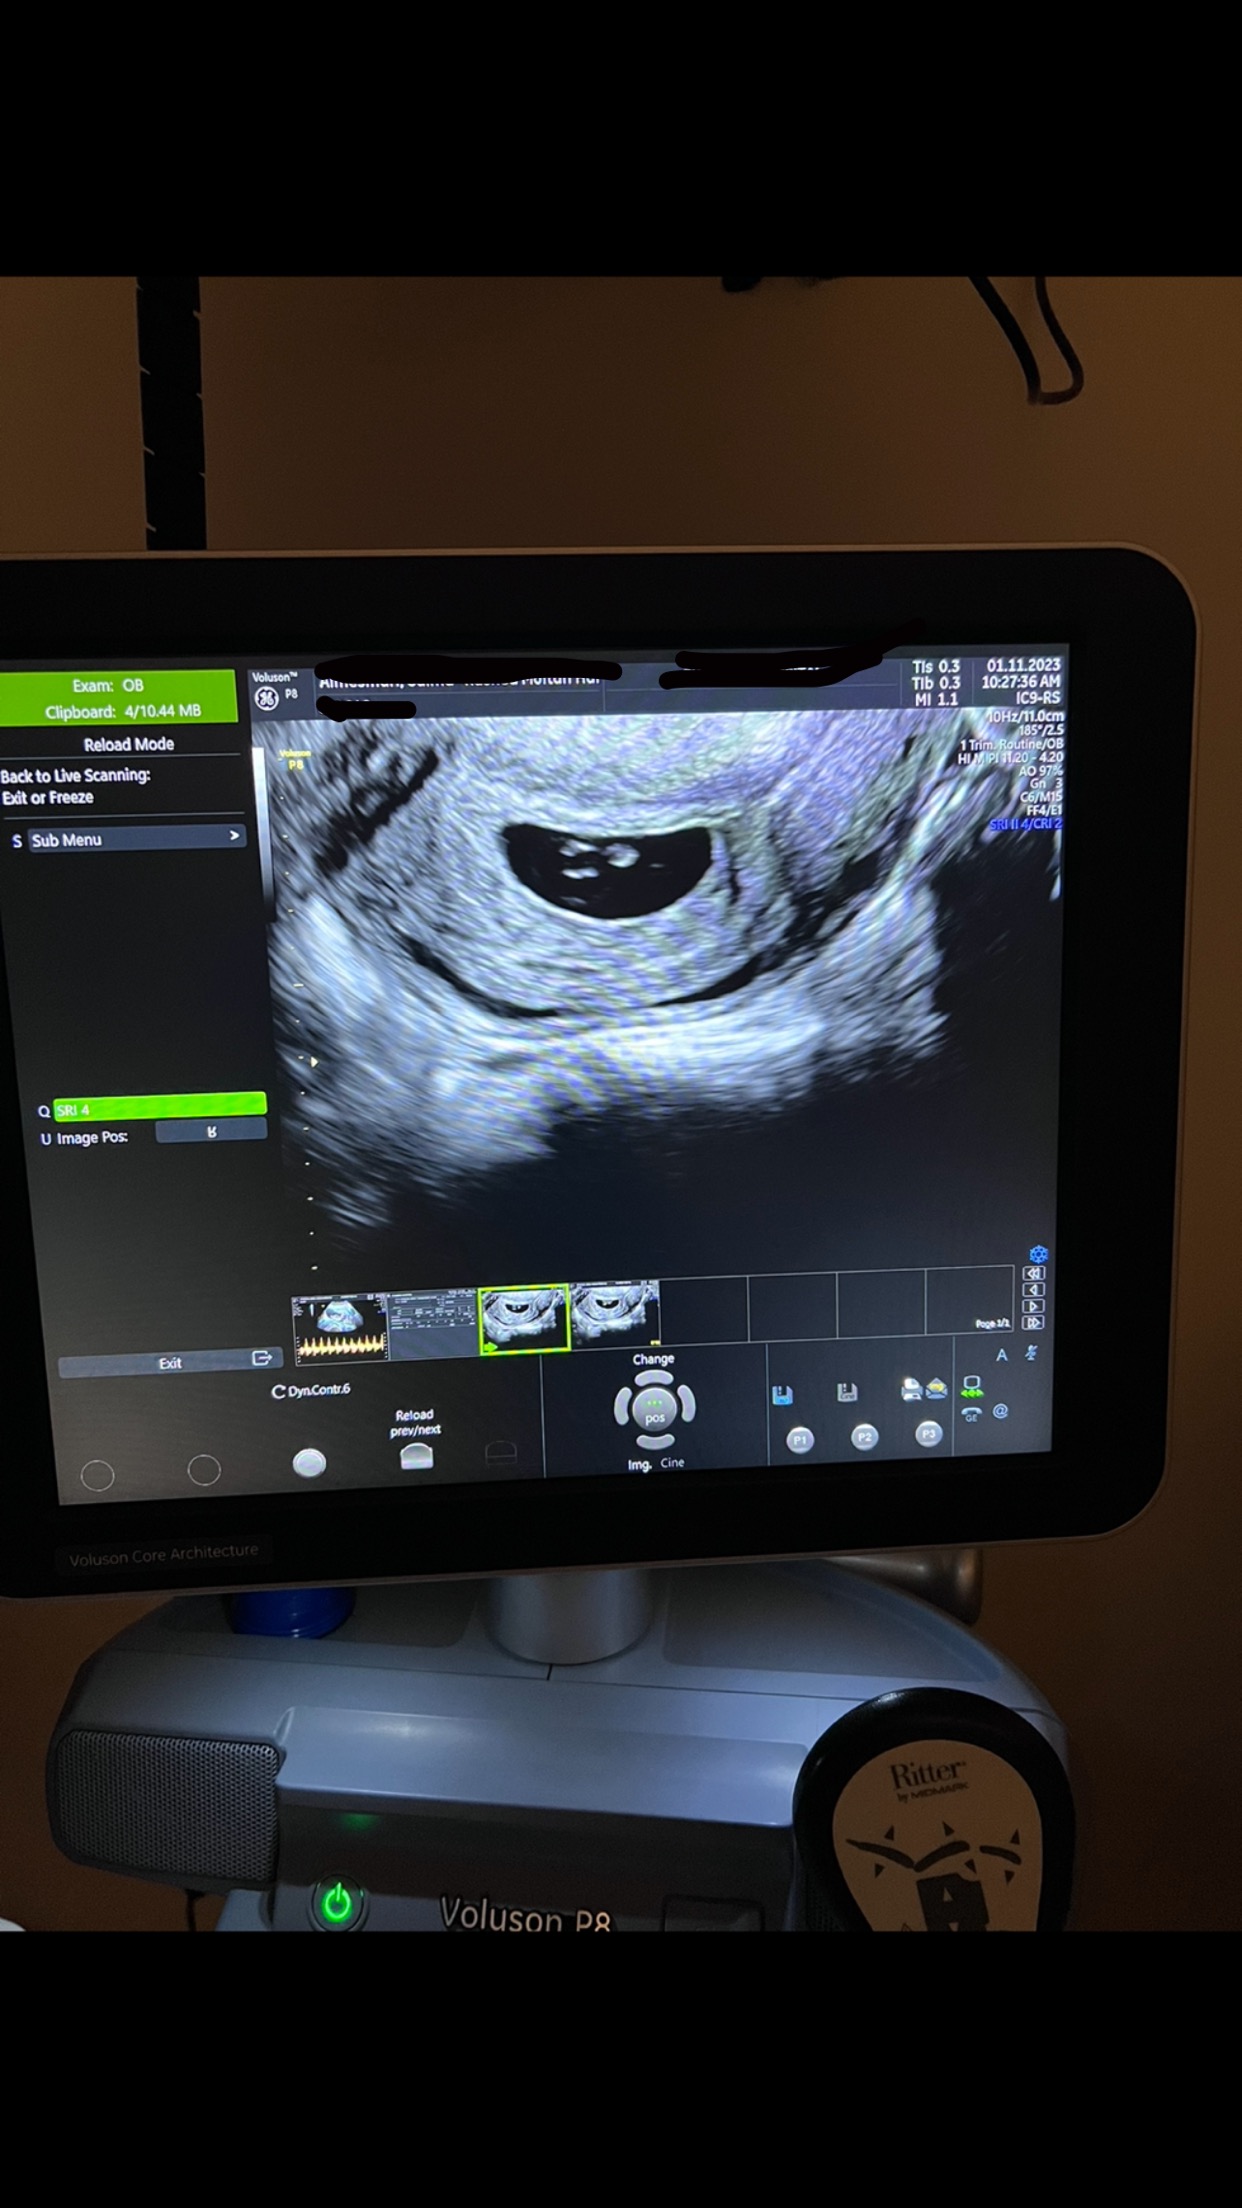

نبض الجنين ما مبين هل هذا الشي طبيعي